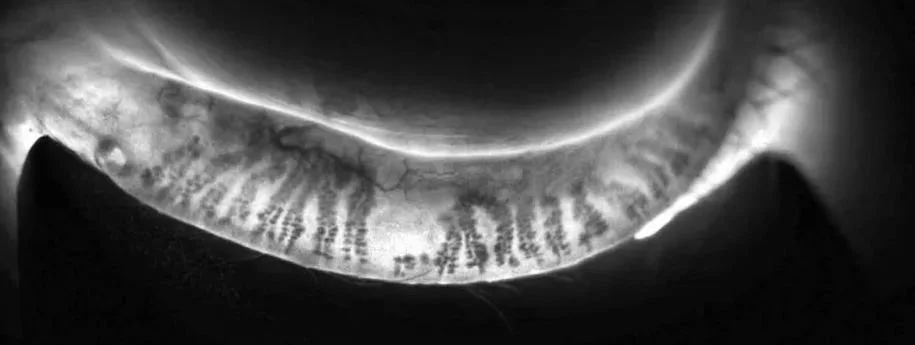

La meibographie est une image représentant l’état des glandes de Meibomius et permettant de détecter des atrophies. Il s’agit d’un test par transillumination grâce auquel nous pouvons identifier une perte partielle ou totale des structures visibles des glandes de Meibomius. La destruction des glandes de Meibomius est la marque de dysfonctionnements meibomiens, mais la meibographie peut aussi être utile pour diagnostiquer d’autres maladies touchant la surface oculaire.

MODIFICATIONS STRUCTURALES DES GLANDES DE MEIBOMIUS